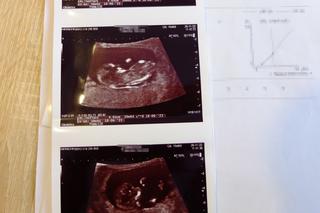

Nazajutrz pojawili się w SPZOZ w Lubartowie ze skierowaniem na usunięcie płodu. Zajął się nią wtedy dr Mohammad Suleiman, który postanowił zbadać ją jeszcze raz. Pojawiła się nadzieja. - Powiedział, że nie widzi żadnej ośmiotygodniowej ciąży, tylko maksymalnie trzytygodniową, co zgadzałoby się z moimi spostrzeżeniami - opowiada kobieta. - Zlecił dodatkowe badania, przestrzegając nas, żebyśmy nie nastawiali się na żadne z rozwiązań. I choć wyniki badań zdawały to potwierdzać, na drugi dzień dwoje innych lekarzy jeszcze raz zbadało pacjentkę, potwierdzając przy okazji rewelacje dr K. - ciąża jest martwa, należy ją usunąć.

- Zaproponowano żonie tabletkę wczesnoporonnną, zdecydowanie odmówiła - dodaje Tomasz Sikora. - Na szczęście, ponieważ po południu tego samego dnia zjawił się u żony dr Suleiman i po kolejnym badaniu potwierdził to co już mówił: dziecko żyje i ma się dobrze. Trzeciego dnia pani Paulina wyszła ze szpitala. Wtedy też dostała SMS od lekarki, która jako pierwsza wydała błędną diagnozę: - Przepraszam, że niepokoję, ale przeanalizowałam pani obraz USG i taki bałagan w macicy może być po implantacji zarodka i dr Suleiman może mieć rację, że to wczesna ciąża, proszę być dobrej myśli..- napisała. Tylko tyle... Po namyśle Sikorowie postanowili poinformować o wszystkim dyrekcję szpitala i Izbę Lekarską w Lublinie.